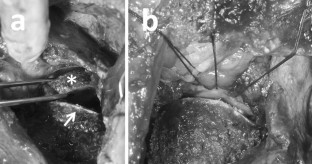

Fig. 1